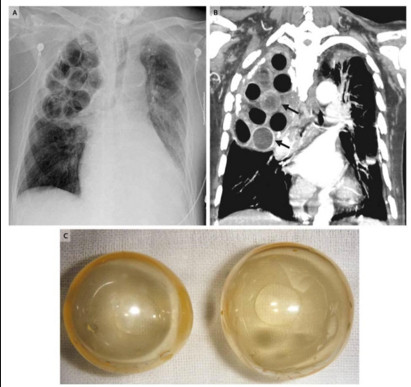

Đầu thế kỷ XX, khi điều trị cho các bệnh nhân lao, các bác sĩ sẽ tiến hành phẫu thuật với hai bước chính.

Theo đó, họ sẽ “đục” những lỗ nhỏ trong phổi bệnh nhân, rồi trám vào đó những… trái bóng nhựa. Các bác sĩ thời đó cho hay, trái bóng nhựa sẽ giúp phần phổi bị nhiễm trùng tự lành trở lại mà không biết rằng đây là một phương pháp phản khoa học. Bởi chỉ có thuốc mới có thể diệt được khuẩn tuberculosis gây ra bệnh lao.

| Chữa nhiễm trùng lao phổ bằng bóng. |

Được biết, sau một khoảng thời gian áp dụng không hiệu quả, phương pháp này dần bị loại bỏ ở phần lớn các nước phát triển.